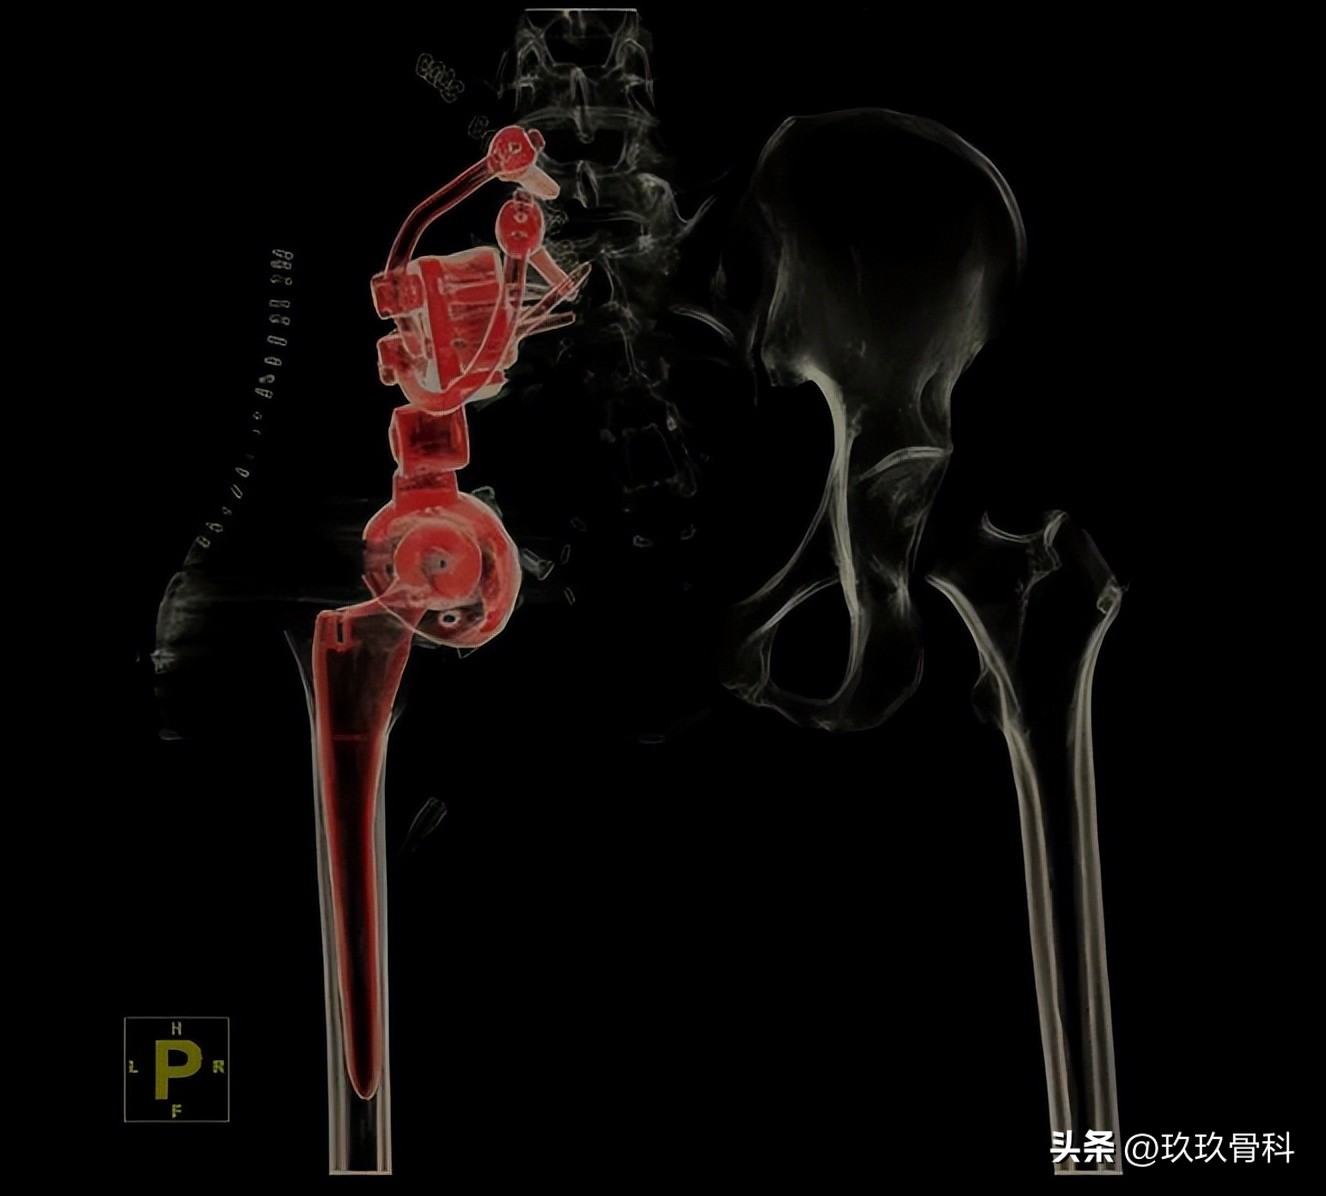

李浩淼主任为其完善相关检查后,确诊为左骨盆肿瘤切除术后半骨盆缺损,团队组织了多学科会诊,制定了完善的手术治疗方案,与力达康肿瘤团队设计了定制化假体假体,最终顺利开展手术,手术进展非常顺利。

术后影像